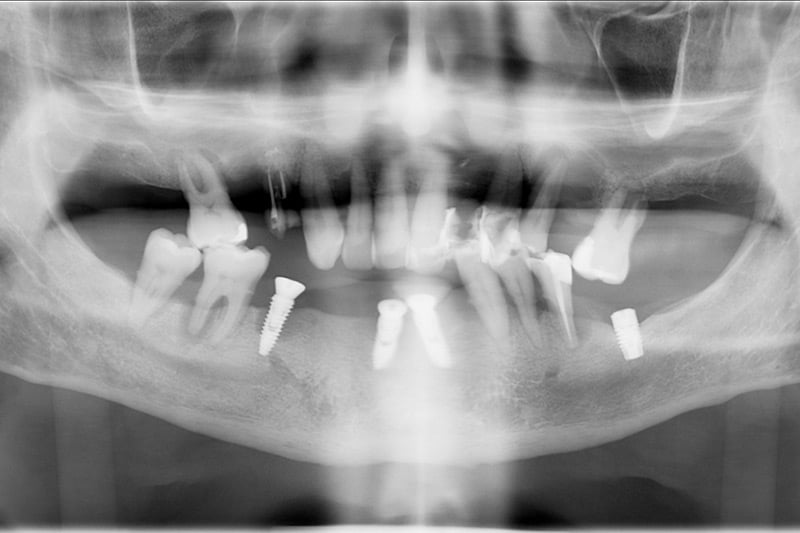

Sin controlar sus problemas de salud oral y de periodontitis, le colocaron implantes dentales, en una posición incorrecta y bajo unas condiciones de salud que propiciaron una infección en esos primeros implantes y por consiguiente la pérdida de hueso y de encía.